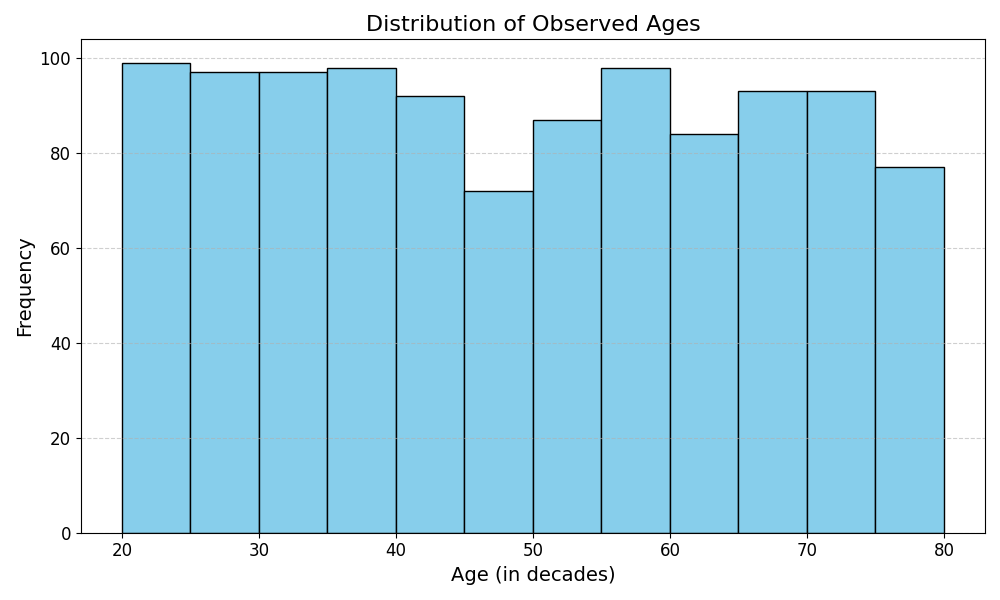

The dataset used consisted of MRI scans from 1220 veterans, aged 20 to 80. For each age between 20 and 80, there were 20 participants, with the exception of three ages: 62, 63, and 64 had 23, 22, and 15 participants, respectively. The cohort was predominantly male, comprising Z % of the data. Aside from sex, no other demographic data was collected.

For the 1104 subjects, their ages were converted to continuous values, capturing fractional years, to improve the regression. Figure 3 illustrates the age distribution of the subset, which appears approximately uniform with slight overrepresentation in younger age groups (20–32) and underrepresentation in the 44–50 age range. The dataset captures a broad age range (20–80 years) with no extreme clustering, suggesting a relatively balanced dataset for analysis.